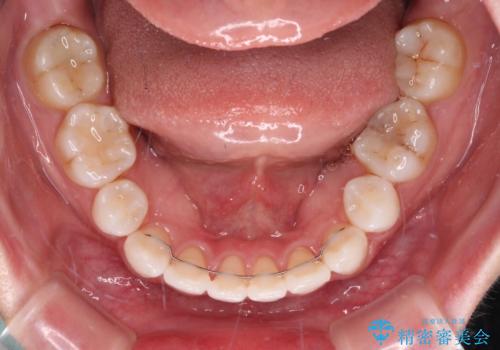

- 口元の突出感と口の閉じにくさを気にして来院された患者様です。

上下左右第一小臼歯4本を抜歯し、ワイヤー装置にて口元を引っ込めるよう矯正治療を行うこととしました。

2年~2年半が治療期間の目安でしたが、順調に治療が進み、1年9か月で満足のいく歯列となりました。